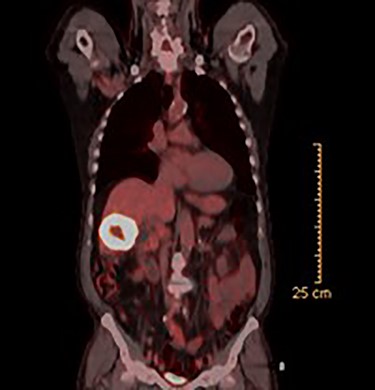

CT guided biopsy of the lesion demonstrated the presence of invasive squamous cell carcinoma with p40-positive and focally positive for CK7 cells. Caris testing was positive for PDL1 (95%) with stable MMR and low TMB. PET scan revealed a large hypermetabolic, centrally necrotic mass involving liver segments V, VI without any abnormal FDG uptake within the head, neck or chest. Pertinent images from the PET scan are demonstrated in Figs 1 and 2.

PET scan (axial view): hypermetabolic, centrally necrotic mass involving liver segment V, VI.